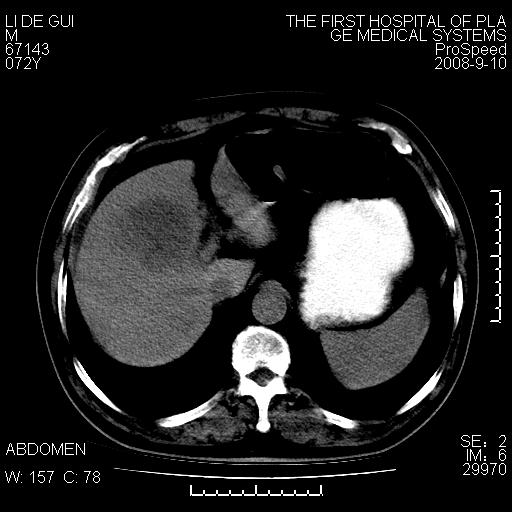

标题: CT17988:腹部肿块两年,肿块大小无变化,患者无不适,自我 [打印本页]

标题: CT17988:腹部肿块两年,肿块大小无变化,患者无不适,自我

胆囊占位性病变(黄色肉芽肿性胆囊炎?)。

考虑-----胆囊血肿机化或胆囊癌或腺肌增生症------增强

胆囊占位性病变,增强。

十二指肠的间质瘤